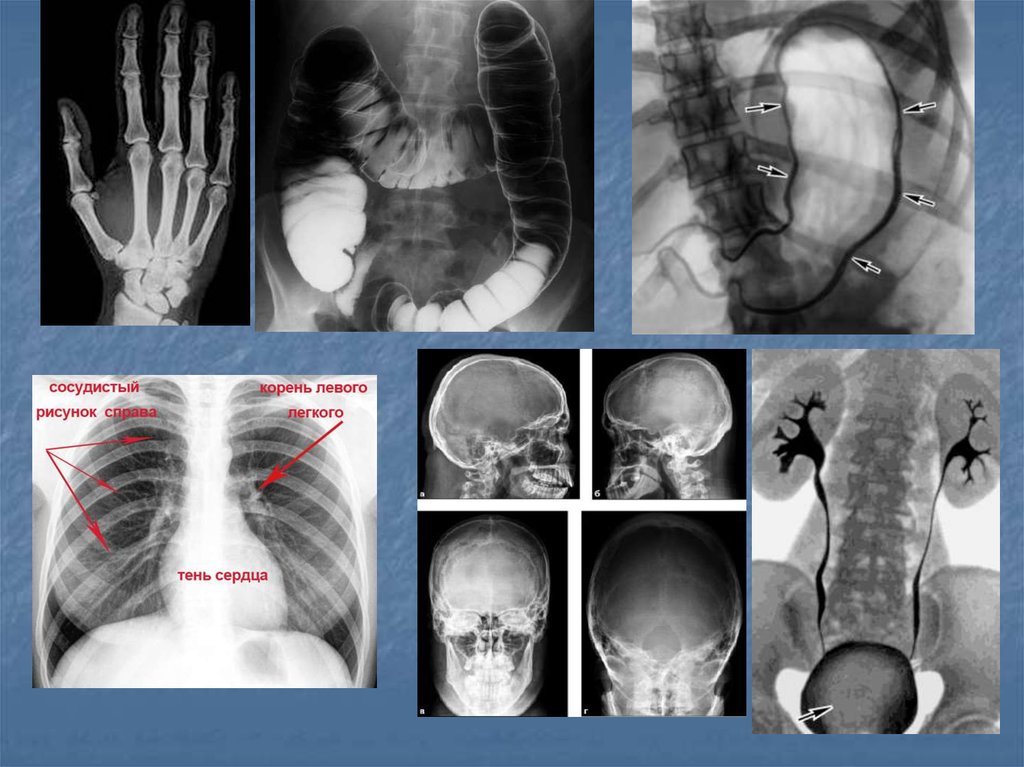

9. Показания

Обзор органов брюшной и грудной полости (наличие

воздуха, жидкости, метастазов, инородный

предметов)

Травма костных структур

Воспалительный процесс(пазухи черепа,

остеомиелит)

Дегенеративные изменения позвоночника и суставов

Рентген-анатомия органов брюшной

полости(желудок, кишечник)

Опухоли ЖКТ, легких, реже головного мозга, костей

Исследование функций почек и

ЖКТ(рентгенография)

Аномалии развития органов грудной и брюшной

полости (мегоколон, долихосигма, болезнь

Гиршпрунга, подковообразная почка, «бычье сердце»

и т.п.)

Скрининг заболеваний легких(флюорография)